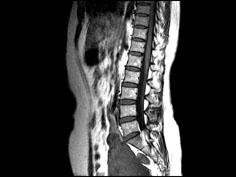

问题 女,37岁,下腹部不适,MRI检查如图所示,下列说法不正确的是 ( )

选项 A、此为子宫粘膜下肌瘤 B、此为子宫浆膜下肌瘤 C、病灶T1信号与子宫肌的信号相同 D、病灶T2信号为明显低信号 E、子宫底部局部隆起,该病灶边界清晰

答案 A